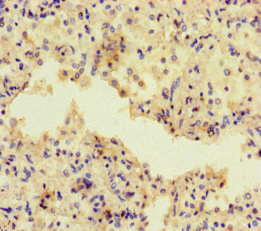

Immunohistochemistry of paraffin-embedded human lung cancer using CSB-PA600142LA01HU at dilution of 1:100